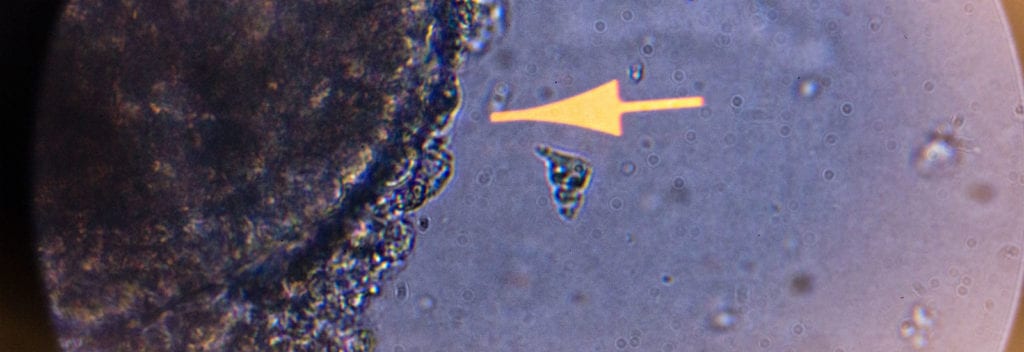

Een virusinfectie in een organoid. Katja Wolthers onderzoekt virussen in proefdiervrije, menselijke modellen.

Gelukkig zijn er wetenschappers die geloven in proefdiervrije innovatie, zoals Katja Wolthers. Katja doet onderzoek naar virussen zonder hier dieren voor in te zetten; al haar onderzoek is gebaseerd op menselijke organoids. Haar ambitie is om in het lab een model te bouwen dat een goede representatie is van de mens. Dat is iets waar ze al jarenlang aan werkt – niet alleen in haar lab in Amsterdam, maar ook via een internationaal trainingsnetwerk genaamd Organovir.